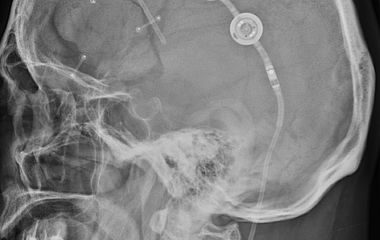

Der Bereich Hydrozephalus, Chiari-Malformation und Tethered-Cord-Syndrom umfasst die Diagnostik und Behandlung komplexer Erkrankungen des Liquorsystems sowie des Gehirns und Rückenmarks. Wir behandeln angeborene und erworbene Formen des Hydrozephalus, einschließlich des Normaldruckhydrozephalus, der sich häufig durch Gangstörungen, kognitive Veränderungen und Blasenfunktionsstörungen äußert. Ein weiterer Schwerpunkt ist die Chiari-Malformation, bei der es zu einer Verlagerung von Kleinhirnanteilen in den Spinalkanal kommen kann und die vielfältige neurologische Symptome verursachen kann. Das Tethered-Cord-Syndrom beschreibt eine krankhafte Fixierung des Rückenmarks, die sowohl in klassischer als auch in okkulter Form auftreten und zu Schmerzen, neurologischen Defiziten oder Funktionsstörungen führen kann. Ziel unserer Behandlung ist es, neuralen Strukturen zu entlasten, eine weitere Schädigung zu verhindern und die Lebensqualität der Patientinnen und Patienten zu verbessern. Grundlage hierfür sind eine präzise Diagnostik, individuell abgestimmte Therapiekonzepte und eine umfassende, verständliche Aufklärung.

Hydrocephalus

Bei Hydrozephalus bieten wir verschiedene Formen der Liquorableitung an, darunter den Liquorshunt und den ventrikuloperitonealen Shunt (VP-Shunt), individuell angepasst an die jeweilige Erkrankung. Als alternative, shuntunabhängige Therapie führen wir die endoskopische Drittventrikulozisternostomie (ETV) durch, sofern die anatomischen Voraussetzungen gegeben sind. Patientinnen und Patienten mit Arnold-Chiari-Malformation behandeln wir durch eine gezielte mikrochirurgische Dekompression, um den Liquorfluss zu verbessern und neurologische Symptome zu lindern. Beim Tethered-Cord-Syndrom, einschließlich okkulter Formen, setzen wir auf ein minimalinvasives Detethering zur schonenden Entlastung des Rückenmarks.